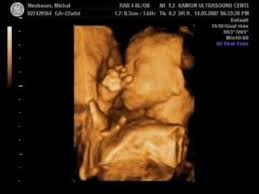

4d ultrasound is a 3d with the time aspect live video of the record. How your baby grows in pregnancy. A 4d ultrasound generates an image that is continuously updated much like a moving image. It is best to think of it with an example.

The main difference is that 3d focuses on the visual effects whereas 4d adds a tangible or tactile aspect to your movie experience. In 4d 3 4 images are taken per second which gives you an illusion of a movie. Or drops of water land on you when iron man flies by the bay. Difference between 3d and 4d images the four dimensional cube tesseract is one example of how the three dimensional world described by x y and z can extend into a fourth one.

3d and 4d ultrasound. A car has three dimensions. A 4d movie is a 3d movie with additional effects providing a real life experience emitted in special cinemas. 3d images are used to show you three dimensional external images that may be helpful in diagnosing issues such as a cleft lip.